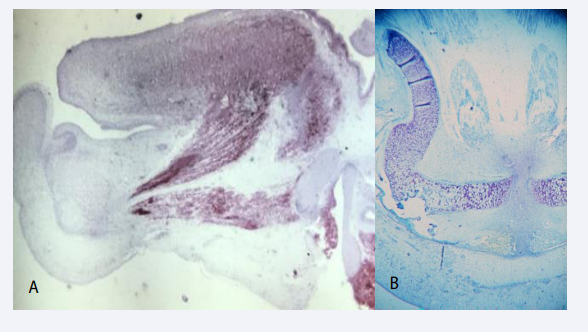

Before development of the mandibular condyle the bilateral bony mandibular components suddenly changed position caused by a muscular contraction by the musculus genio-glossis and musculus genio-hyoideus [Figure 8A].

Figure 8 A: Mid-sagittal section through the tongue in a human fetus 12 weeks of Gestation. The red color express NGFR ( Nerve growth Factor  Receptor) indicating muscle activity. Two muscle bundles appear active. The upper is the genioglossus muscle and the lower the geniohyoid  muscle. Contraction of these two muscles results in a backward and downward move of the tongue and mandible. These physiological processes  are responsible for creating space for the maxillary shelves to elevate and fuse during palate formation. B: Histological horizontal section of the mandible, Gestational age 13 weeks, demonstrating the S-shape of the Mekel’s cartilage, which is a result  of the backward drawing of the mandible by muscular traction (see figure A).

This contraction moves the jaw components backward resulting in an enlarged distance between the distal parts of the mandibular components [9-11]. This movement occur exactly when the maxillary palatal shelves change from a vertical to a horizontal position, forming the palate. This backward movement of the tongue and mandible necessary for forming the palate can be observed in the S-shape of the Meckels cartilage [Figure 8B].